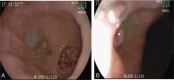

Diagnoses: Contrast medium permeated into the gastric cavity through a fistula between the abdominal aorta and gastric tube at the 11th thoracic level, Based on this, we made a diagnosis of AGF resulting from a peptic ulcer, and this diagnosis was further confirmed by high pressure angiography combined with computed tomography (CT) imaging.